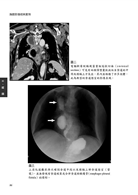

病例7 肝細胞癌(Hepatocellular carcinoma) 33